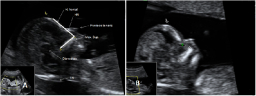

Con la ecografía de la semana 12 de embarazo se pueden detectar algunos signos (marcadores) característicos de los fetos con alguna anomalía cromosómica. Uno de ellos es el ángulo que forman el maxilar superior y el hueso frontal. Qué mide el ángulo frontomaxilar del bebé Se mide el ángulo...

Ecografía de la translucencia nucal

La ecografía de la derecha muestra a un bebé con un cribado positivo que resultó tener un síndrome de Down. La translucencia nucal (o pliegue nucal) por ecografía se ve como un espacio negro en la parte posterior del cuello, acotado por las marcas del ecografista. El bebé de la izquierda...

Ecografía para medir al feto

En la ecografía 2D de este feto de 12 semanas, podemos apreciar la medida cráneo-caudal o CRC (desde la cabeza hasta la rabadilla o coxis), que en este caso es de 6,2 centímetros. Estirado, el bebé mide más -algo más de 10 centímetros-, pero los especialistas suelen tomar esta medida, más...